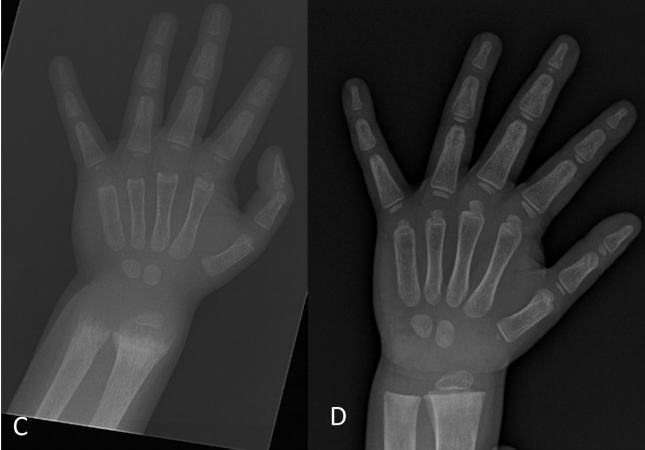

TABLE 3. (just the top)

Image

When examining another polymorphism at the ApaI site, peak torque in eccentric knee

Studies assessing the relation between VDR polymorphisms, falls, muscle function, and markers of insulin 2374 extensors at 120°/sec was significantly lower in the AA homozygous group compared with the aa and Aa groups.